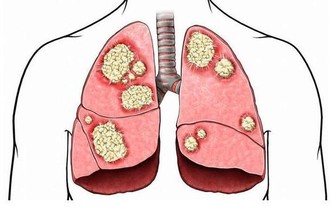

8.拿著重物上下樓梯時,是否感到吃力?

如果發現自己才爬幾層樓就氣很喘、呼吸困難,往往肺功能已經比正常人差了。平時工作中,你可利用打電話和午休的時間上下樓。上下樓梯時要注意多運用大腿肌肉、臀部肌肉和腹肌力量。